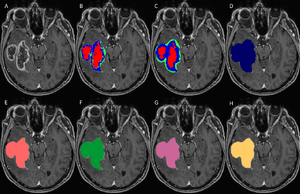

Fully Automated Enhanced Tumor Compartmentalization: Man vs. Machine Reloaded

Publication: PLoS One. 2016 Nov 2;11(11):e0165302. PMID: 27806121 | PDF Authors: Porz N, Habegger S, Meier R, Verma R, Jilch A, Fichtner J, Knecht U, Radina C, Schucht P, Beck J, Raabe A, Slotboom J, Reyes M, Wiest R. Institution: Support Center for Advanced Neuroimaging, Institute for Diagnostic and Interventional Neuroradiology, University Hospital and University of Bern, Bern, Switzerland. Background/Purpose: Comparison of a fully-automated segmentation method that uses compartmental volume information to a semi-automatic user-guided and FDA-approved segmentation technique. METHODS: Nineteen patients with a recently diagnosed and histologically confirmed glioblastoma (GBM) were included and MR images were acquired with a 1.5 T MR scanner. Manual segmentation for volumetric analyses was performed using the open source software 3D Slicer version 4.2.2.3. Semi-automatic segmentation was done by four independent neurosurgeons and neuroradiologists using the computer-assisted segmentation tool SmartBrush® (referred to as SB), a semi-automatic user-guided and FDA-approved tumor-outlining program that uses contour expansion. Fully automatic segmentations were performed with the Brain Tumor Image Analysis (BraTumIA, referred to as BT) software. We compared manual (ground truth, referred to as GT), computer-assisted (SB) and fully-automated (BT) segmentations with regard to: (1) products of two maximum diameters for 2D measurements, (2) the Dice coefficient, (3) the positive predictive value, (4) the sensitivity and (5) the volume error. RESULTS: Segmentations by the four expert raters resulted in a mean Dice coefficient between 0.72 and 0.77 using SB. BT achieved a mean Dice coefficient of 0.68. Significant differences were found for intermodal (BT vs. SB) and for intramodal (four SB expert raters) performances. The BT and SB segmentations of the contrast-enhancing volumes achieved a high correlation with the GT. Pearson correlation was 0.8 for BT; however, there were a few discrepancies between raters (BT and SB 1 only). Additional non-enhancing tumor tissue extending the SB volumes was found with BT in 16/19 cases. The clinically motivated sum of products of diameters measure (SPD) revealed neither significant intermodal nor intramodal variations. The analysis time for the four expert raters was faster (1 minute and 47 seconds to 3 minutes and 39 seconds) than with BT (5 minutes). CONCLUSION: BT and SB provide comparable segmentation results in a clinical setting. SB provided similar SPD measures to BT and GT, but differed in the volume analysis in one of the four clinical raters. A major strength of BT may its independence from human interactions, it can thus be employed to handle large datasets and to associate tumor volumes with clinical and/or molecular datasets ("-omics") as well as for clinical analyses of brain tumor compartment volumes as baseline outcome parameters. Due to its multi-compartment segmentation it may provide information about GBM subcompartment compositions that may be subjected to clinical studies to investigate the delineation of the target volumes for adjuvant therapies in the future. |

Set of MRI sequences used in this study for manual, automatic, and semi-automatic tumor volumetry. Original T1-weighted post-contrast MRI slice (A), manual subcompartmental segmentation into non-enhancing tumor (green), enhancing tumor (blue), and necrotic tissue (red) (B). BT subcompartmental segmentation into non-enhancing tumor (green), enhancing tumor (blue) and necrotic tissue (red) (C). BT core tumor segmentation (dark blue, D), SB1 core tumor segmentation (light red, E), SB2 core tumor segmentation (green, F), SB3 core tumor segmentation (purple, G) and SB4 core tumor segmentation (yellow, H). |